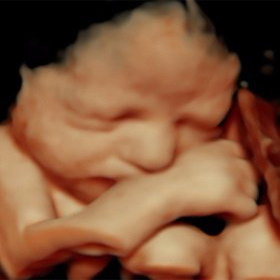

3D/4D ultrasound is an advanced imaging technique that provides a more detailed and lifelike view of a developing fetus compared to traditional 2D ultrasound.